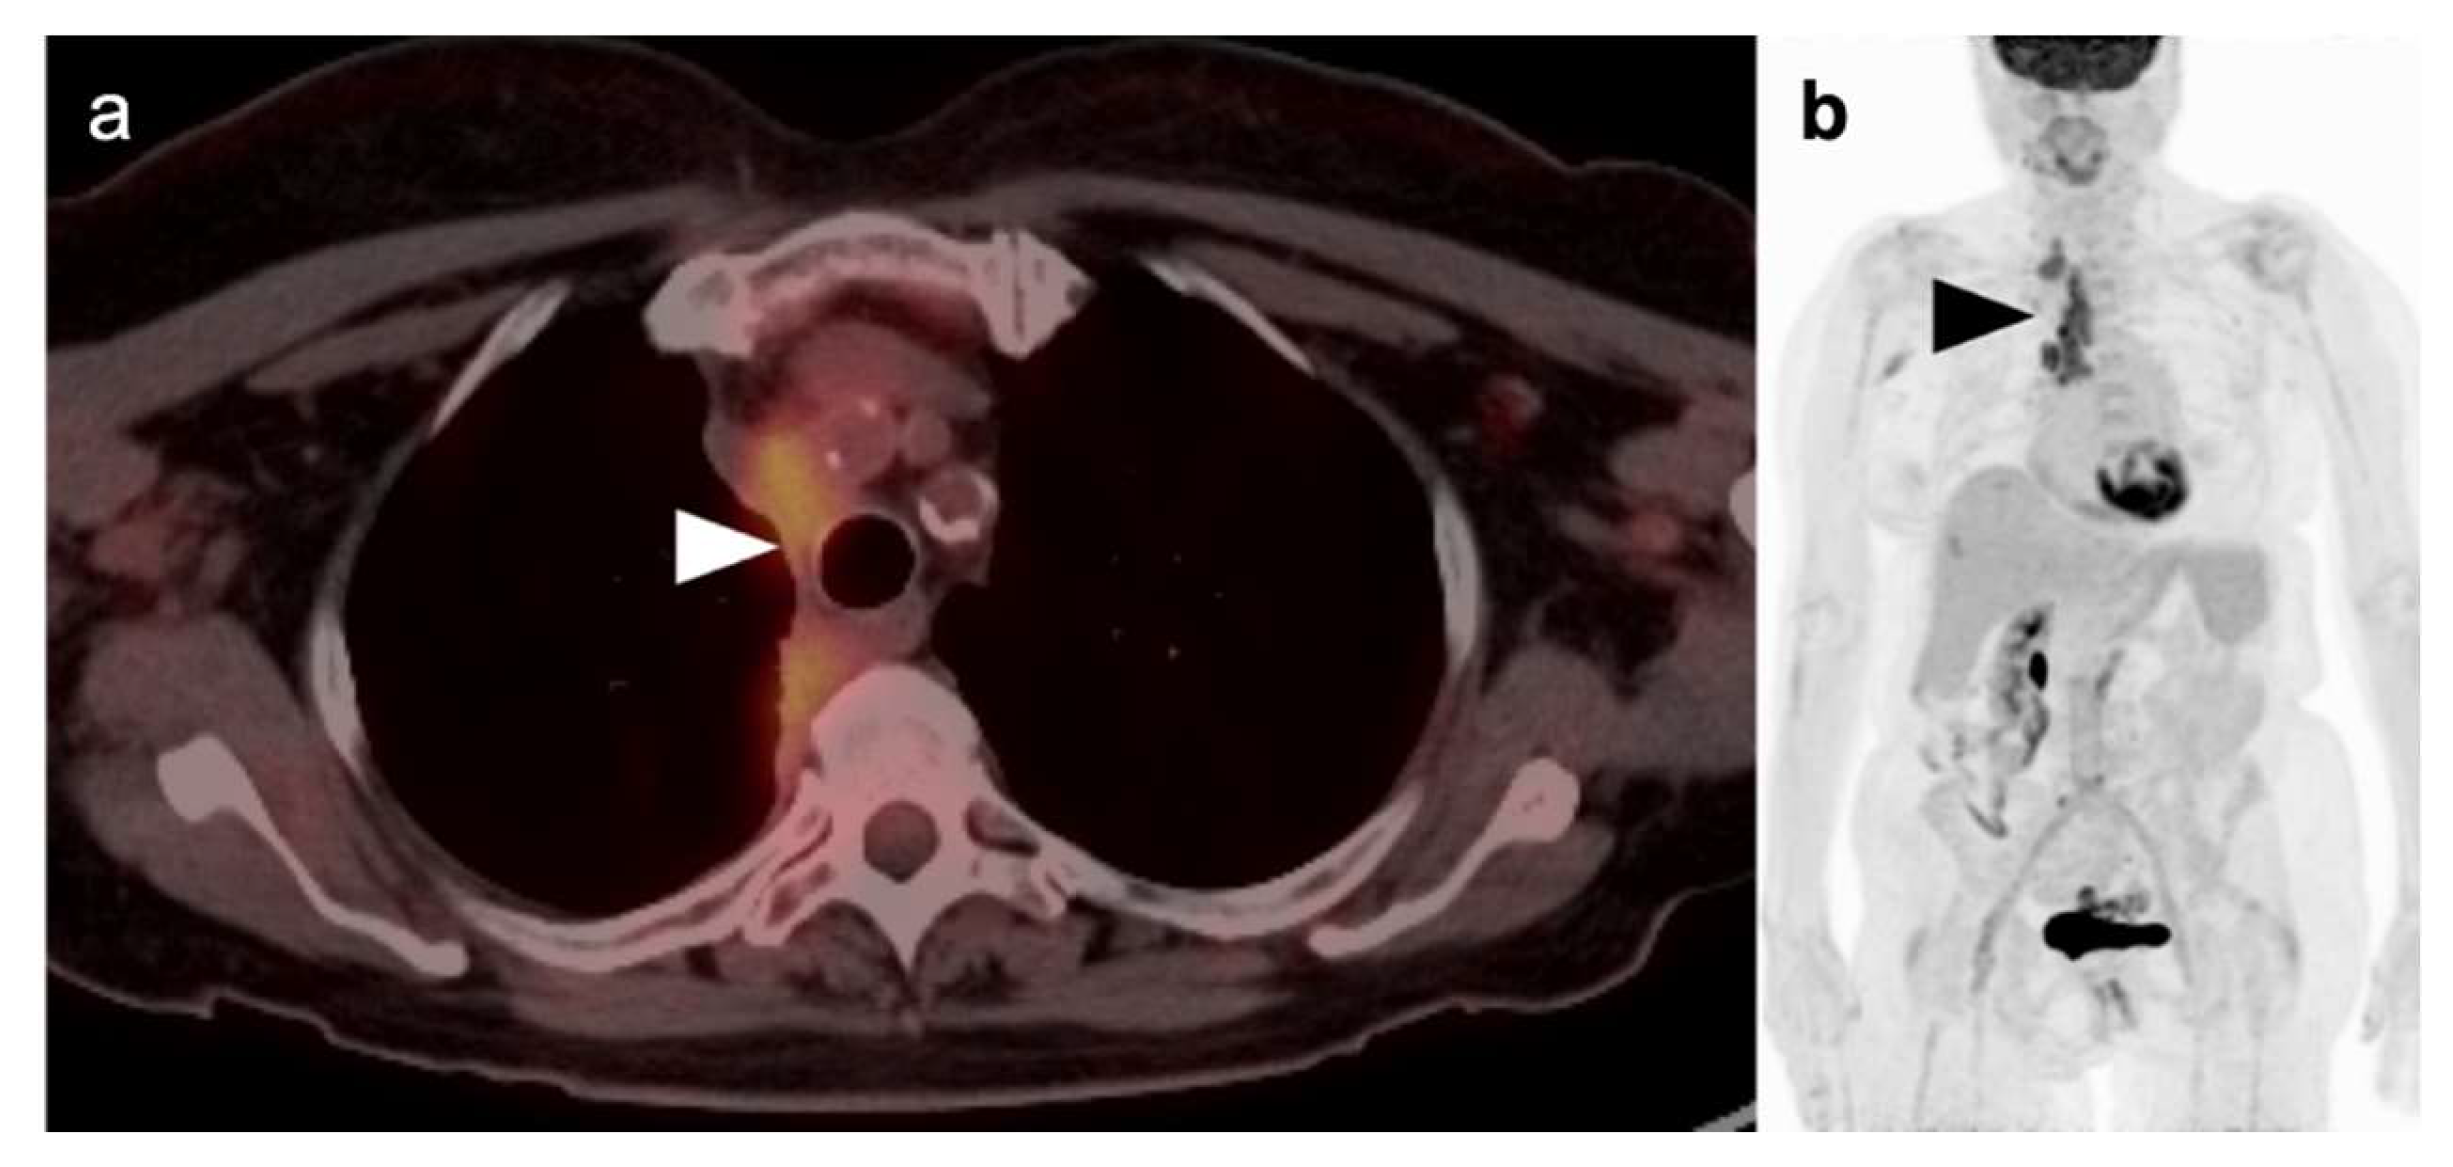

Anterior mediastinal masses present a challenge to both conventional imaging and FDG PET-CT. There is a relatively large variation in the size of the thymus in normal individuals. In those younger in age, and those with thymic hyperplasia and thymic stimulation, a mass-like appearance of the thymus may be present and can be moderately hypermetabolic on FDG PET-CT. Many types of tumors may present, or be associated with, anterior mediastinal masses [56]. These include mature and immature teratomas and other germ cell tumors, lymphoma, salivary-type tumors, and metastatic disease. Substernal thyroid tissue can also masquerade as a thymic neoplasm. In general, thymoma tends to be lower in metabolic activity on FDG PET-CT than is thymic carcinoma (Figure 16). However, attempts to utilize FDG PET-CDT to distinguish hyperplastic thymic tissue, benign thymoma, and thymic carcinoma, and the assessment of varying grades of each have been met with variable success [57]. Kumar et al. report the mean metabolic activity (SUVmax) of thymic masses: thymic hyperplasia (SUVmax 1.1), thymoma (SUVmax 2.3), and thymic carcinoma (SUVmax 7.0) [58]. They further reported that an SUVmax of 6.5 could differentiate between thymoma and thymic carcinoma with a sensitivity and specificity of 100% and 87.2% (Figure 16) [59]. Others have reported that FDG PET-CT can distinguish between thymoma and thymic carcinoma but not between thymomas of various grades [60]. However, other reports suggest that metabolic activity alone cannot distinguish between all grades of thymoma [61]. Thymic neuroendocrine tumors tend to be mild in uptake of FDG and may be better imaged by 68Ga or 64Cu DOTATATE PET [62].

In summary, the use of FDG PET-CT in the characterization of anterior mediastinal masses, and to distinguish between various grades of thymoma and thymic carcinoma is an imperfect process. Accurate interpretation requires comparison with prior imaging, clinical information, anatomic imaging characterization, and, ultimately, histological analysis in many cases. In staging thymic carcinoma, the value of FDG PET-CT is still not firmly established [63]. The best use of FDG PET-CT is likely in identifying distant metastases.